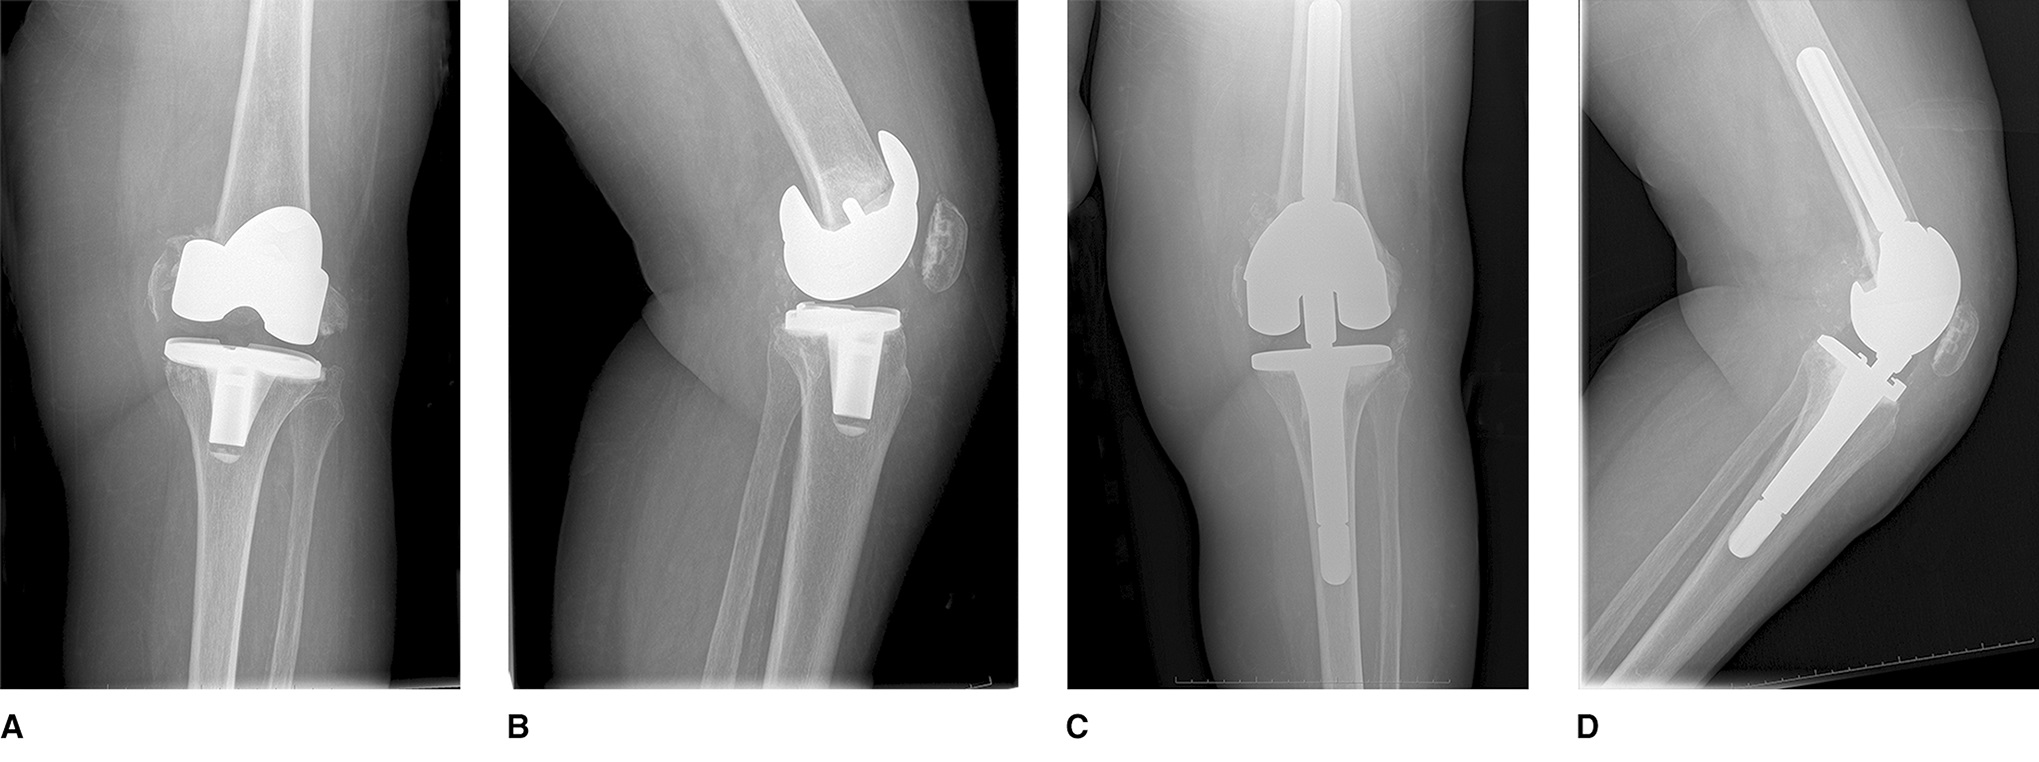

If there is not sufficient bone at the end of the femur, your surgeon may use a special type of implant known as distal femoral replacement.

Periprosthetic distal femur fracture treated with a distal femur arthroplasty.

Reproduced and adapted from Bengoa F, Neufeld M, Howard L, Masri B. Periprosthetic Fractures After a Total Knee Arthroplasty. J Am Acad Orthop Surg 2023; 31[19]:e746-e759.